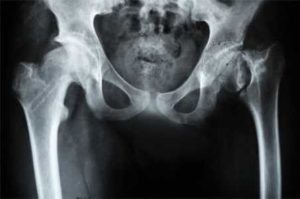

Диагностические мероприятия для подтверждения диагноза должен проводить квалифицированный доктор. Комплекс медикаментов и физиотерапевтических процедур составляется строго лечащим врачом.

Большинство больных узнает о своей болезни непосредственно на второй стадии, когда степень патологии можно считать средне-тяжелой. Именно коксартроз 2 степени дает о себе знать выраженностью симптоматики. Начальный этап редко обнаруживается, так как человек не ощущает на себе тяжести появляющейся проблемы.

- суставная щель значительно уменьшается, образующиеся костные разрастания создают трение, вызывая боль при движении;